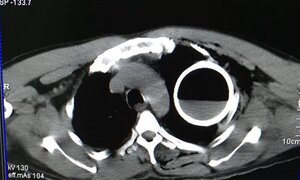

Bệnh nhân ngã cầu thang, bị một dị vật chưa xác định đâm vào vùng lõm xương đòn và mắc trong ngực, gây khó thở; sau khi chụp X quang và CT, các bác sĩ ngỡ ngàng khi thấy một vỏ chai thuỷ tinh còn nguyên vẹn trong lồng ngực bệnh nhân.